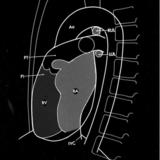

Right chambers PA

Date: 03/02/2006

Views: 2342